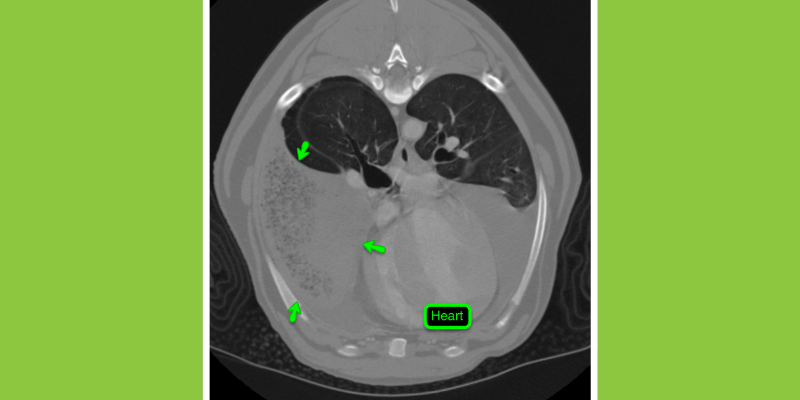

CT image of the chest of a dog that was experiencing difficulty breathing. The lung lobe in the lower right has less air (less black) due to twisting of the lung causing lung lobe torsion. This is a surgical emergency requiring rapid detection and removal of the abnormal lung lobe.